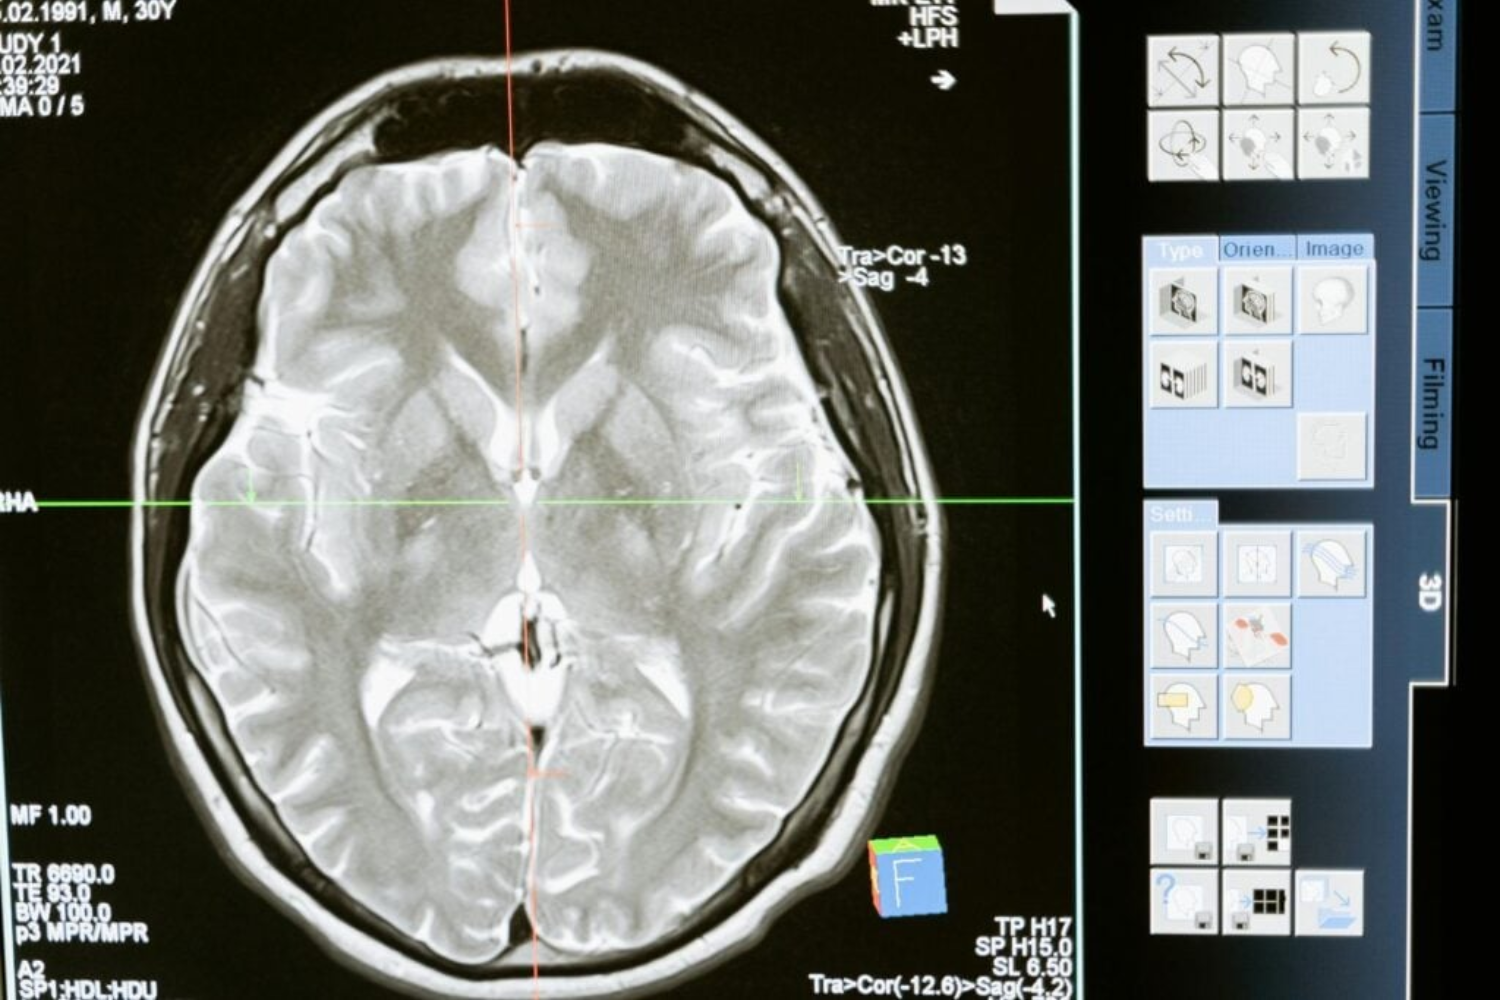

Essas placas — formadas por fragmentos de proteínas que se acumulam entre os neurônios — estão associadas à inflamação cerebral e à perda de memória.

Os testes em culturas celulares e modelos animais mostraram melhorias notáveis em memória, orientação espacial e aprendizado, além da reversão de alterações bioquímicas típicas do Alzheimer.

Os ratos tratados tiveram melhor desempenho em tarefas de memória e aprendizado, além de apresentarem níveis mais equilibrados de cobre no hipocampo, região crucial para o armazenamento de lembranças.